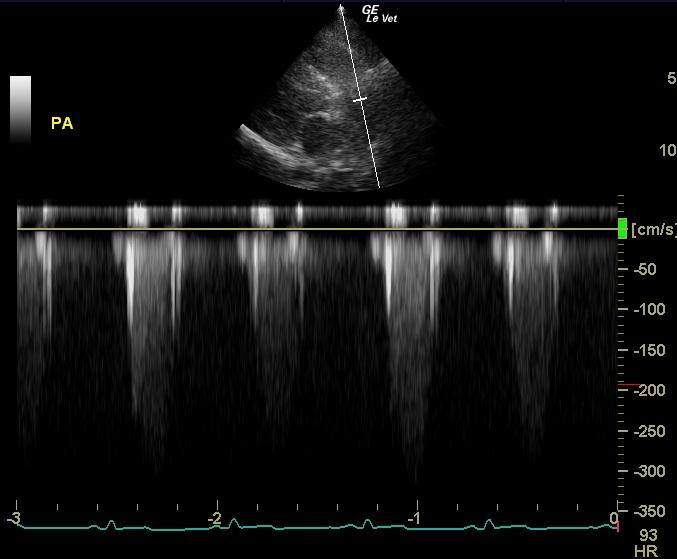

An 11-year-old MN Golden retriever was presented for evaluation due to two episodes of collapse and cyanosis. Additional history was that the patient was more lethargic than usual. Cardiac auscultation did not reveal any abnormalities and blood pressure was normal. Survey radiographs showed a mildly enlarged cardiac silhouette (VHS 11), prominent right ventricle, normal left atrial, and a normal lung pattern.